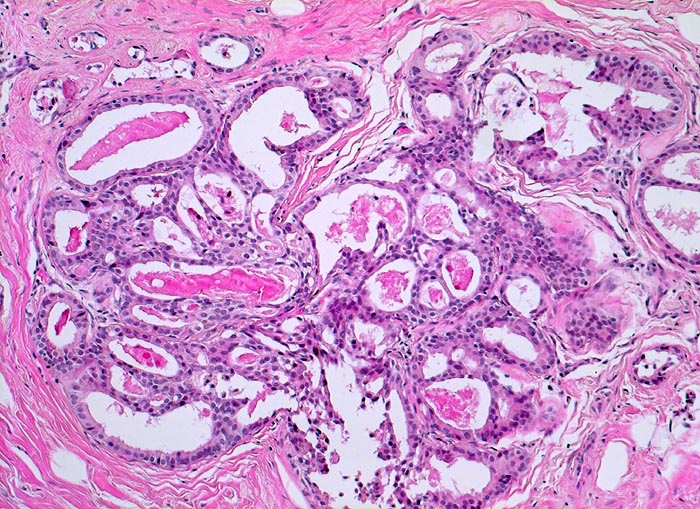

• Ausgeprägte Fibrose und zystisch erweiterte Gangstrukturen in organoider Anordnung.

• Kolumnarzellveränderung: erweiterte Drüsen ausgekleidet von hochprismatischem Epithel mit apikalen Nasen (snouts) gefüllt mit Sekret und teilweise assoziiert mit Mikrokalk.

• Im Zentrum des Präparates stark erweiterte Gänge mit intraduktalen peripheren Papillomen.

• Alle Drüsen zeigen eine erhaltene äussere abgeflachte Myoepithelschicht mit hellem Zytoplasma.